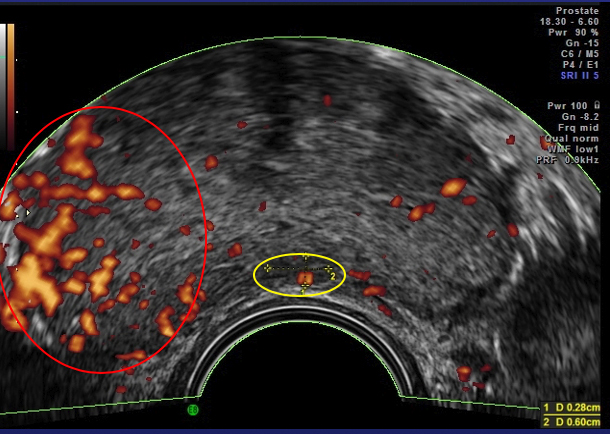

In 1994 Prof. Francois Cornud in Paris developed a better way to sample the tissue of the prostate using Doppler ultrasound. Sound waves are reflected by different tissues at different speeds, creating an image. These doppler images show tumor vascular flow the same way the Weather Doppler shows tornadoes. The presence of tumor-related blood vessels poses a hazard during the biopsy, where they can be inadvertently “nicked,” resulting in bleeding, and their presence indicates a more serious, “aggressive,” tumor. Effective cancer therapies shrink these arteries, making this 10-minute examination both safer and a means of indirectly monitoring treatment.

Since prostate cancer is, in many instances, slow-growing, early cases are often managed by watchful waiting, without invasive surgery or chemotherapy. Ultrasound imaging that detects increased tumor vascularity allows patients with biopsy-proven cancers to come in for regular scans to see if their disease is stable or if more aggressive treatment is indicated.

These technologies can focus the doppler’s sound waves on specific areas and additional data describing blood flow obtained. This data can be combined to generate a quantitative reading of the tumor vessel density to serve as a treatment guide. Vessel density of 15% is found in aggressive cancers requiring intervention, while densities of 1-2% are noted in most low-grade tumors, that can simply be monitored.

chemotherapy are conventional alternatives. It is advisable to seek medical opinions on personalized healing options as side effects occur and treatment is best individually tailored. Recurrence may occur following successful initial therapy with any treatment modality, and Doppler ultrasound with MRI is useful in detecting any regrowth as this image shows.